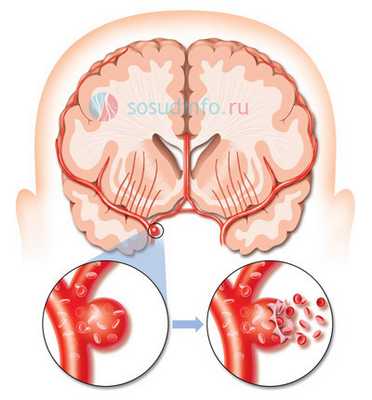

Аневризма сосудов головного мозга - это серьезное заболевание, при котором в стенке артерий головного мозга образуется локальное выпячивание, обусловленное истончением и потерей эластичности пораженного участка стенки. Как показывает статистика, с данной патологией сталкивается около 5% населения. При отсутствии лечения она может осложняться таким жизнеугрожающим состоянием, как разрыв аневризмы. Основным методом лечения этой болезни является хирургическое вмешательство. В данное статье мы поговорим о такой оперативной технике, как клипирование аневризмы сосудов головного мозга.

Клипирование аневризм сосудов головного мозга является довольно сложной операцией, требующей проведения трепанации черепа. Суть данного метода заключается в наложении специального устройства, называемого клипсой, на шейку аневризмы с внешней стороны сосуда. Таким образом патологически измененный участок отсекается от общего кровотока.

Аневризма - это патология, которая характеризуется расширением просвета сосуда, выпячиванием сосудистой стенки и формированием аневризматического мешка, обусловленная воздействием факторов врожденного или приобретенного характера. Как правило, аневризма развивается в стенке артерий, а не вен, и чаще всего локализуется в сосудах головного мозга и в аорте.

Клипирование аневризмы головного мозга - это наложение специального устройства, называемого клипсой, на шейку аневризмы с внешней стороны сосуда. Такая операция является одной из самых сложных в нейрохирургии и проводится с помощью открытого доступа - трепанации черепа.